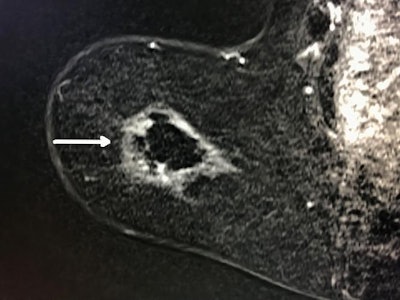

Cryoablation offers a new way to treat the disease. For the procedure, a probe is inserted into the tumor through an incision in the skin using local anesthesia. The clinician uses ultrasound to guide the probe; once it is in place, liquid nitrogen is delivered to the tumor. During an initial, eight-minute freezing cycle, the nitrogen forms an ice ball that surrounds the tumor and destroys it. After a thaw cycle, the clinician performs another eight-minute freeze cycle to make sure all of the cancer cells are eradicated. The procedure takes less than an hour, Tomkovich said.

Freezing the tumor has advantages over heating it, one of which is that the tissue retains its shape when frozen, making it easier to eliminate the tumor completely, according to the researchers.